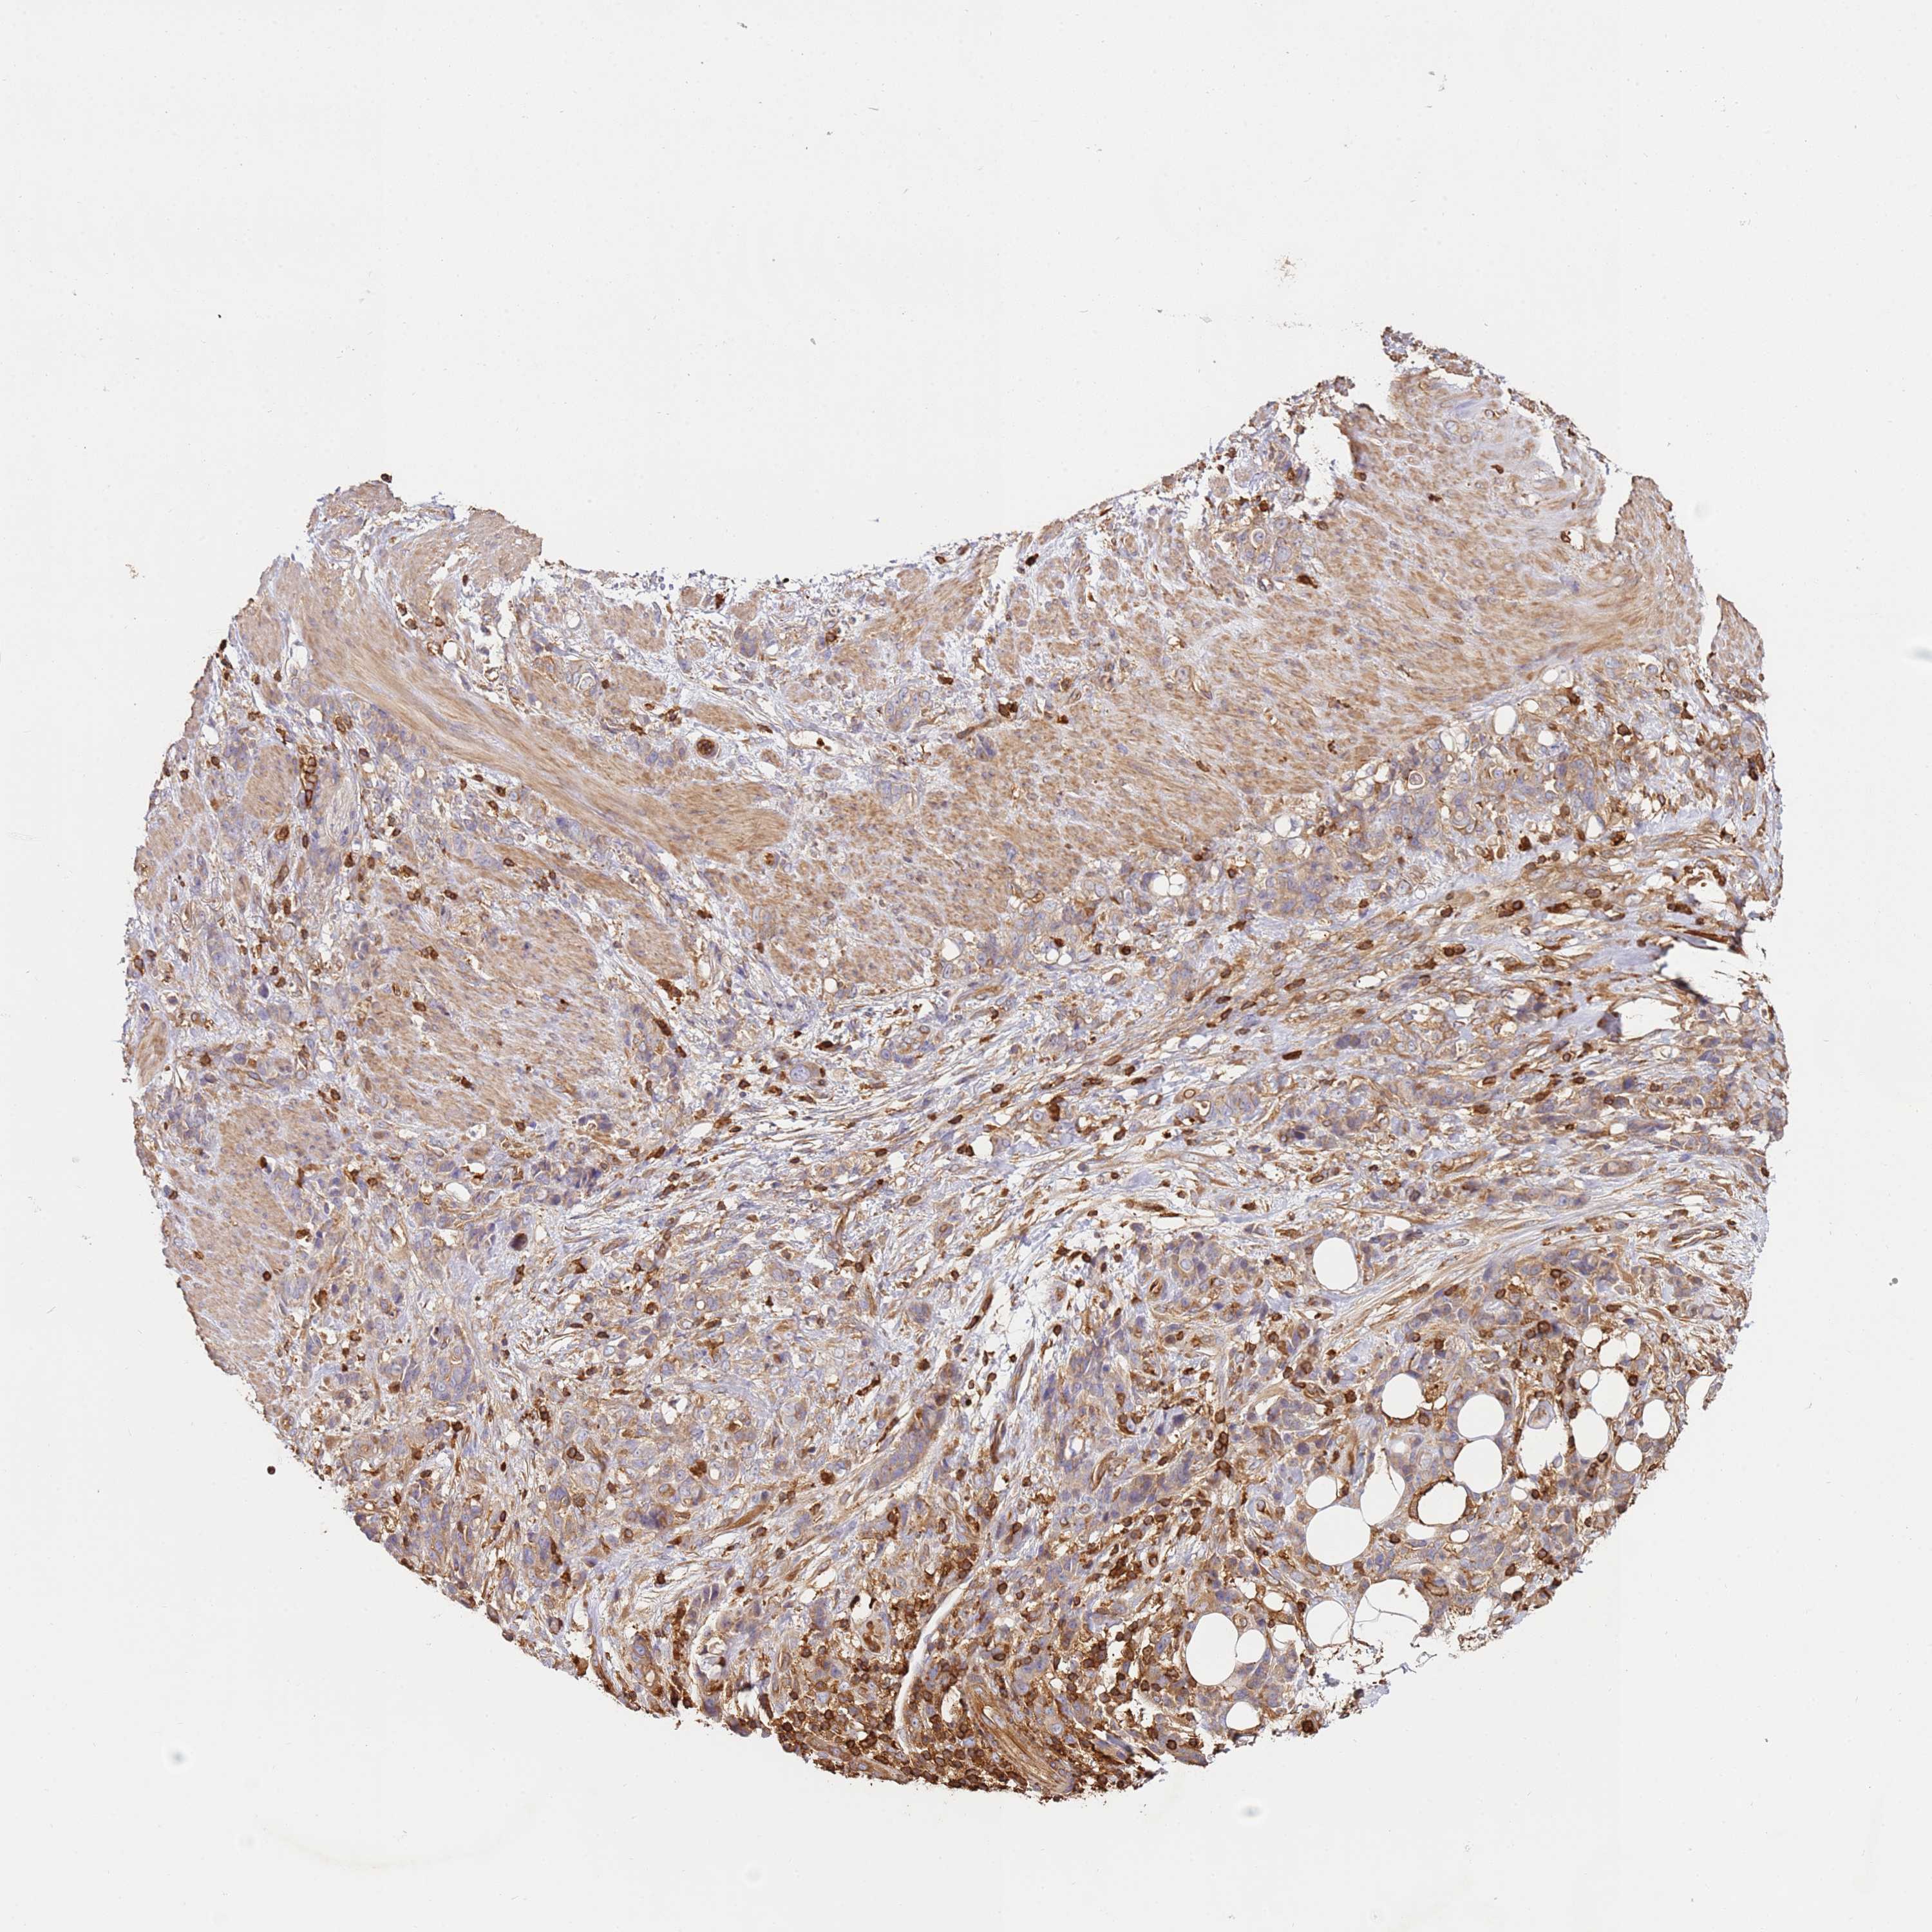

STOMACH CANCER - Protein expressioni

A mouse-over function shows sample information and annotation data. Click on an image to view it in a full screen mode. Samples can be filtered based on level of antibody staining by selecting one or several of the following categories: high, medium, low and not detected. The assay and annotation is described here.

Note that samples used for immunohistochemistry by the Human Protein Atlas do not correspond to samples in the TCGA dataset.

Antibody stainingi

Antibody staining in the annotated cell types in the current human tissue is reported as not detected, low, medium, or high, based on conventional immunohistochemistry profiling in selected tissues. This score is based on the combination of the staining intensity and fraction of stained cells.

Each image is clickable and will lead to virtual microscopy that enables deeper exploration of all samples and also displays staining intensity scores, fraction scores and subcellular localization as well as patient and tissue information for each sample.

Antibody HPA047466

Staining

High

Medium

Low

Not detected

Intensity

Strong

Moderate

Weak

Negative

Quantity

>75%

75%-25%

<25%

None

Location

Nuclear

Cytoplasmic/membranous

Cytoplasmic/membranous,nuclear

Adenocarcinoma, NOS